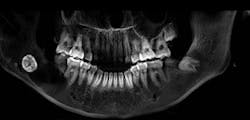

A 13-year-old male was noted by his orthodontist to have an expanding radiolucency encompassing impacted tooth no. 11. The patient was without complaint, and his medical history was otherwise unremarkable. A CT scan revealed a multilocular radiolucency extending from the maxillary midline to the area of the left permanent second molar and expanding into the left maxillary sinus. Cortical expansion in the area of the lesion was notable and all adjacent teeth were vital.

Treatment for case no. 2

The keratocystic odontogenic tumor of the left maxilla presented a much more complicated scenario for this patient as complete removal via enucleation and curettage would require removal of permanent teeth nos. 9–15, and most of the associated alveolus. The floor of the maxillary sinus was obliterated by the cyst as well, so complete removal in this fashion would have resulted in a near hemimaxillectomy, producing a catastrophic defect for this patient. This defect would not have been just physically difficult to endure, but given the patient’s age, psychologically devastating as well.

These factors prompted a decision to treat this lesion with marsupialization, with a plan to later enucleate any residual lesion. Marsupialization involves opening the cavity of the cyst and suturing the lining to the oral mucosa, creating a permanent opening from the cyst cavity into the oral cavity. Once this is complete, the cyst will typically slowly decrease in size via appositional bone formation at the periphery of the cavity. Once the cavity has sufficiently decreased in size, the remaining lesion can be removed via enucleation and curettage as described in the first case.

At the time of publication, the lesion described had reduced in size dramatically, now extending from tooth nos. 10–12. The floor of the maxillary sinus ossified as well. The time elapsed since the marsupialization procedure was six months. Removal of the residual cyst with immediate bone grafting would be performed shortly, likely including the sacrifice of the lateral incisor and second bicuspid. Although this is a large defect, it will be much more easily managed than that posed if marsupialization had not been utilized (figure 7).